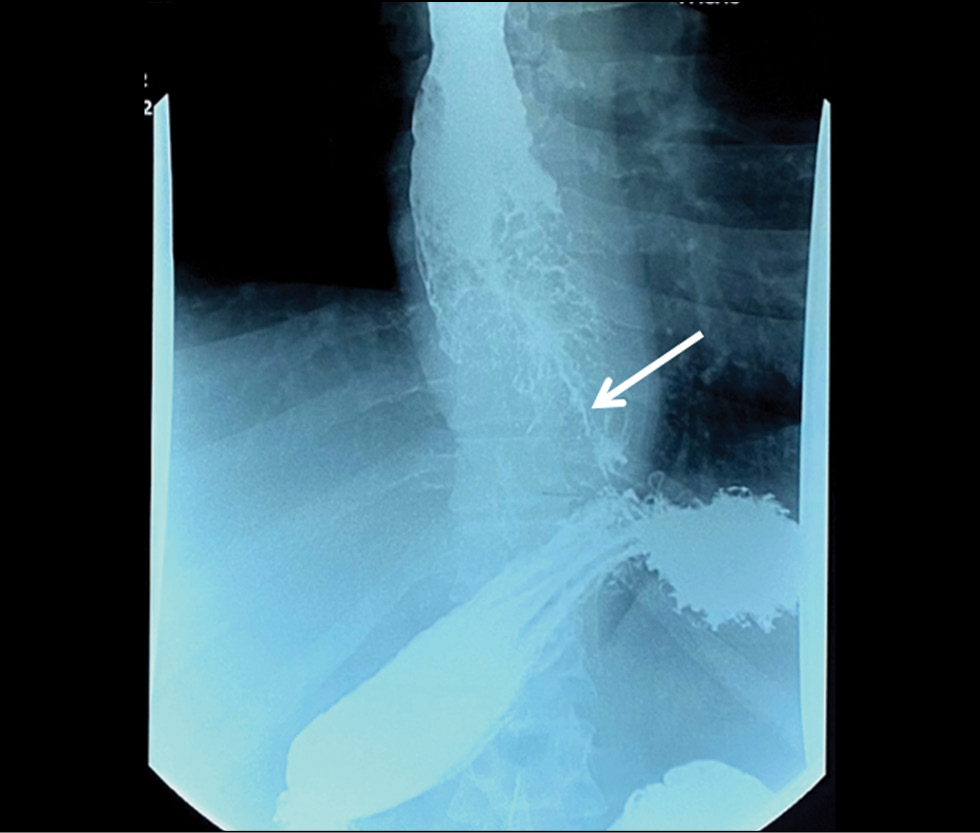

Tissue sampling and histopathological limitations in esophageal cancer

Esophageal adenocarcinoma is a common gastrointestinal cancer. Esophagogastroduodenoscopy with biopsy and immunohistochemistry are used to detect the neoplasm at an early stage. Definitive diagnosis requires not only highly specialized equipment but also the skills of the endoscopist and pathologist. We report the case of a 35-year-old man with progressive dysphagia caused by gastroesophageal cancer. Numerous esophagogastroduodenoscopy studies, computed tomography, and barium X-ray swallow revealed an extensive esophageal lesion; however, pathomorphologic examinations did not confirm malignancy within a year. Histological studies showed pyloric gland adenoma and adenoma from parietal or oncocytic cells with high-grade dysplasia. Esophagogastroduodenoscopy with targeted biopsy at a specialized center confirmed the tumor malignancy. This clinical case demonstrates the importance of summing clinical symptoms and using additional instrumental methods to make a definitive diagnosis if biopsy results are ambiguous.